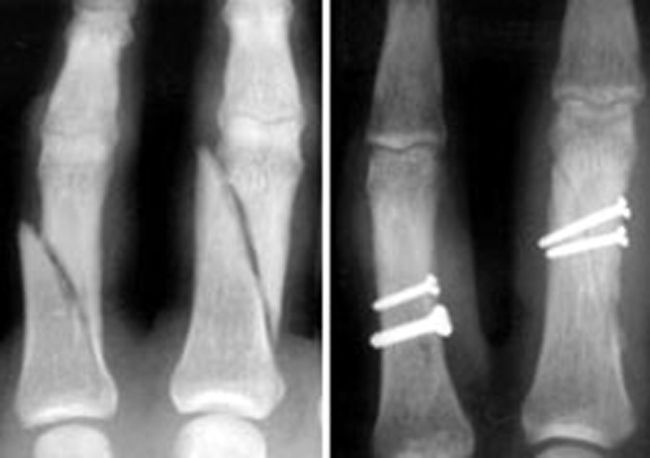

Phalanx fractures and internal fixation

(Left) X-ray shows fractures in the phalanges of two fingers. (Right) In this X-ray, the fractures have been repaired with screws.

Reproduced from Kozin SH, Thoder JJ, Lieberman G: Operative Treatment of Metacarpal and Phalangeal Shaft Fractures. J Am Acad Orthop Surg 2000; 8:111-121.